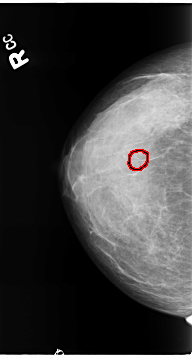

B_3119_1.RIGHT_CC

RIGHT_CC LINES 4648 PIXELS_PER_LINE 2496 BITS_PER_PIXEL 12 RESOLUTION 50 OVERLAY

FILE: B_3119_1.RIGHT_CC.OVERLAY

TOTAL_ABNORMALITIES 1

ABNORMALITY 1

LESION_TYPE CALCIFICATION TYPE PLEOMORPHIC DISTRIBUTION CLUSTERED

ASSESSMENT 4

SUBTLETY 3

PATHOLOGY BENIGN

TOTAL_OUTLINES 1

BOUNDARY